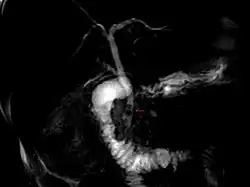

| Magnetic resonance cholangiopancreatography (MRCP) image of two gallstones in the distal common bile duct | |

The diagnosis of choledocholithiasis is suggested when the liver function blood test shows an elevation in bilirubin and serum transaminases. Other indicators include raised indicators of ampulla of vater (pancreatic duct obstruction) such as lipases and amylases. In prolonged cases the international normalized ratio (INR) may change due to a decrease in vitamin K absorption. (It is the decreased bile flow which reduces fat breakdown and therefore absorption of fat soluble vitamins). The diagnosis is confirmed with either a magnetic resonance cholangiopancreatography (MRCP), an endoscopic retrograde cholangiopancreatography (ERCP), or an intraoperative cholangiogram. If the patient must have the gallbladder removed for gallstones, the surgeon may choose to proceed with the surgery, and obtain a cholangiogram during the surgery. If the cholangiogram shows a stone in the bile duct, the surgeon may attempt to treat the problem by flushing the stone into the intestine or retrieve the stone back through the cystic duct.